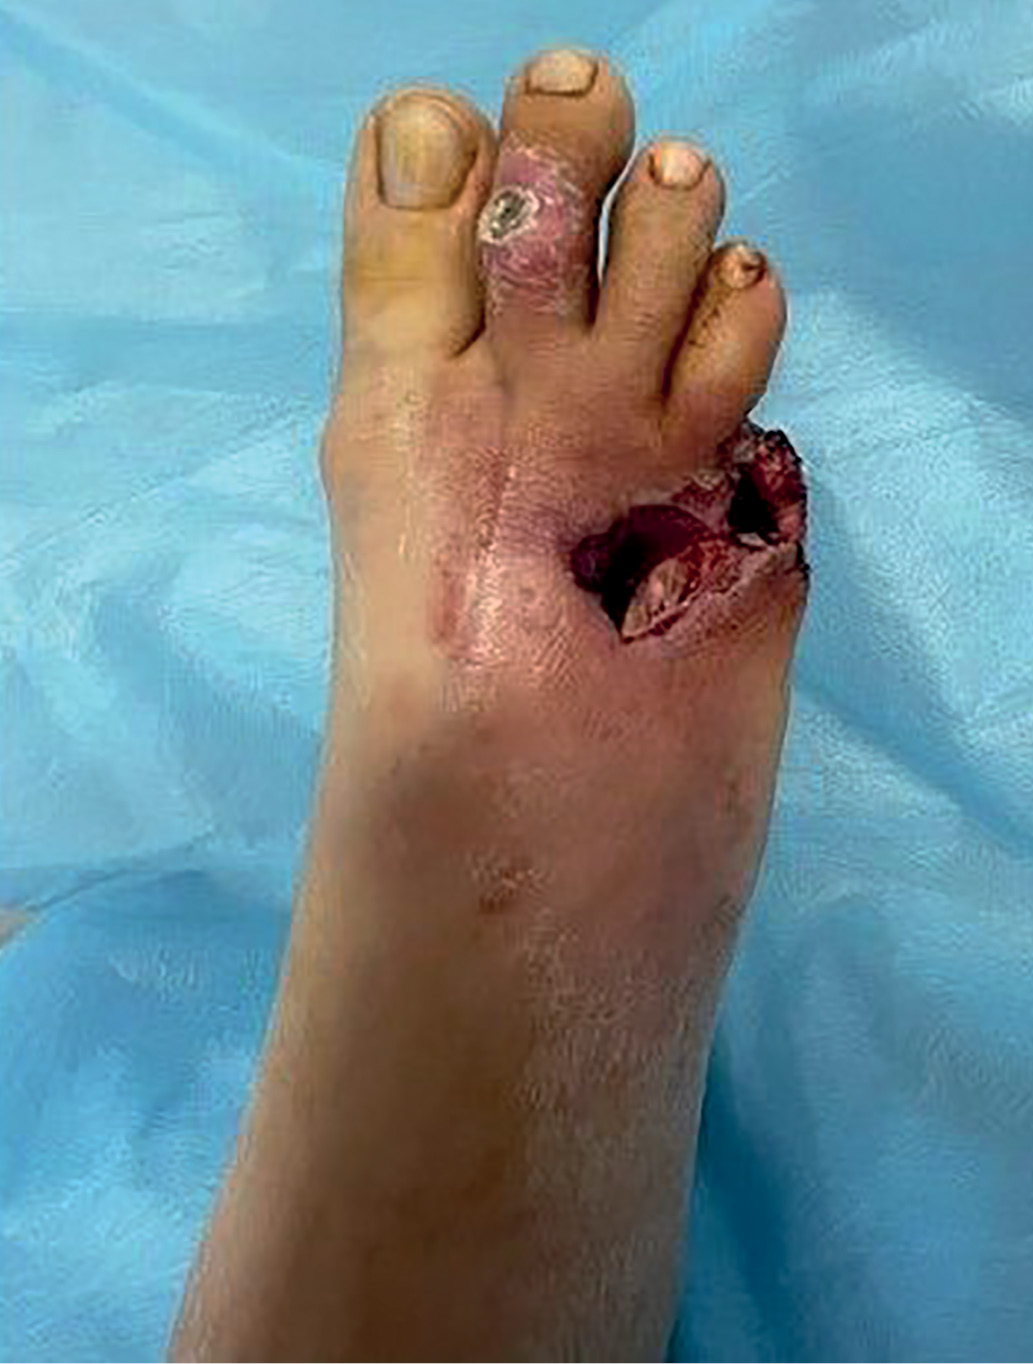

Рентгенография правой стопы (рис. 3).

Рисунок 3. Рентгенограмма. Остеомиелит головок 4 и 5 плюсневых костей.

Заключение: определяется состояние после ампутации 5 пальца (фаланг). Остеомиелит головок 4 и 5 плюсневых костей.

Отмечаются признаки диффузного остеопороза, кистозно-фиброзной перестройки костей предплюсны, эпиметафизов косточек плюсны, фаланг, признаки деформирующего артроза в межфаланговых суставах, в 1-м плюснефаланговом суставе, в суставе Лисфранка. Экзостоз ногтевой фаланги 1 пальца по медиальной поверхности. Сосуды правой стопы обызвествлены. Раневой дефект мягких тканей в проекции 5 плюсневой кости. Кальциноз плюсневых и пальцевых артерий. Мягкие ткани отечны и неоднородны.